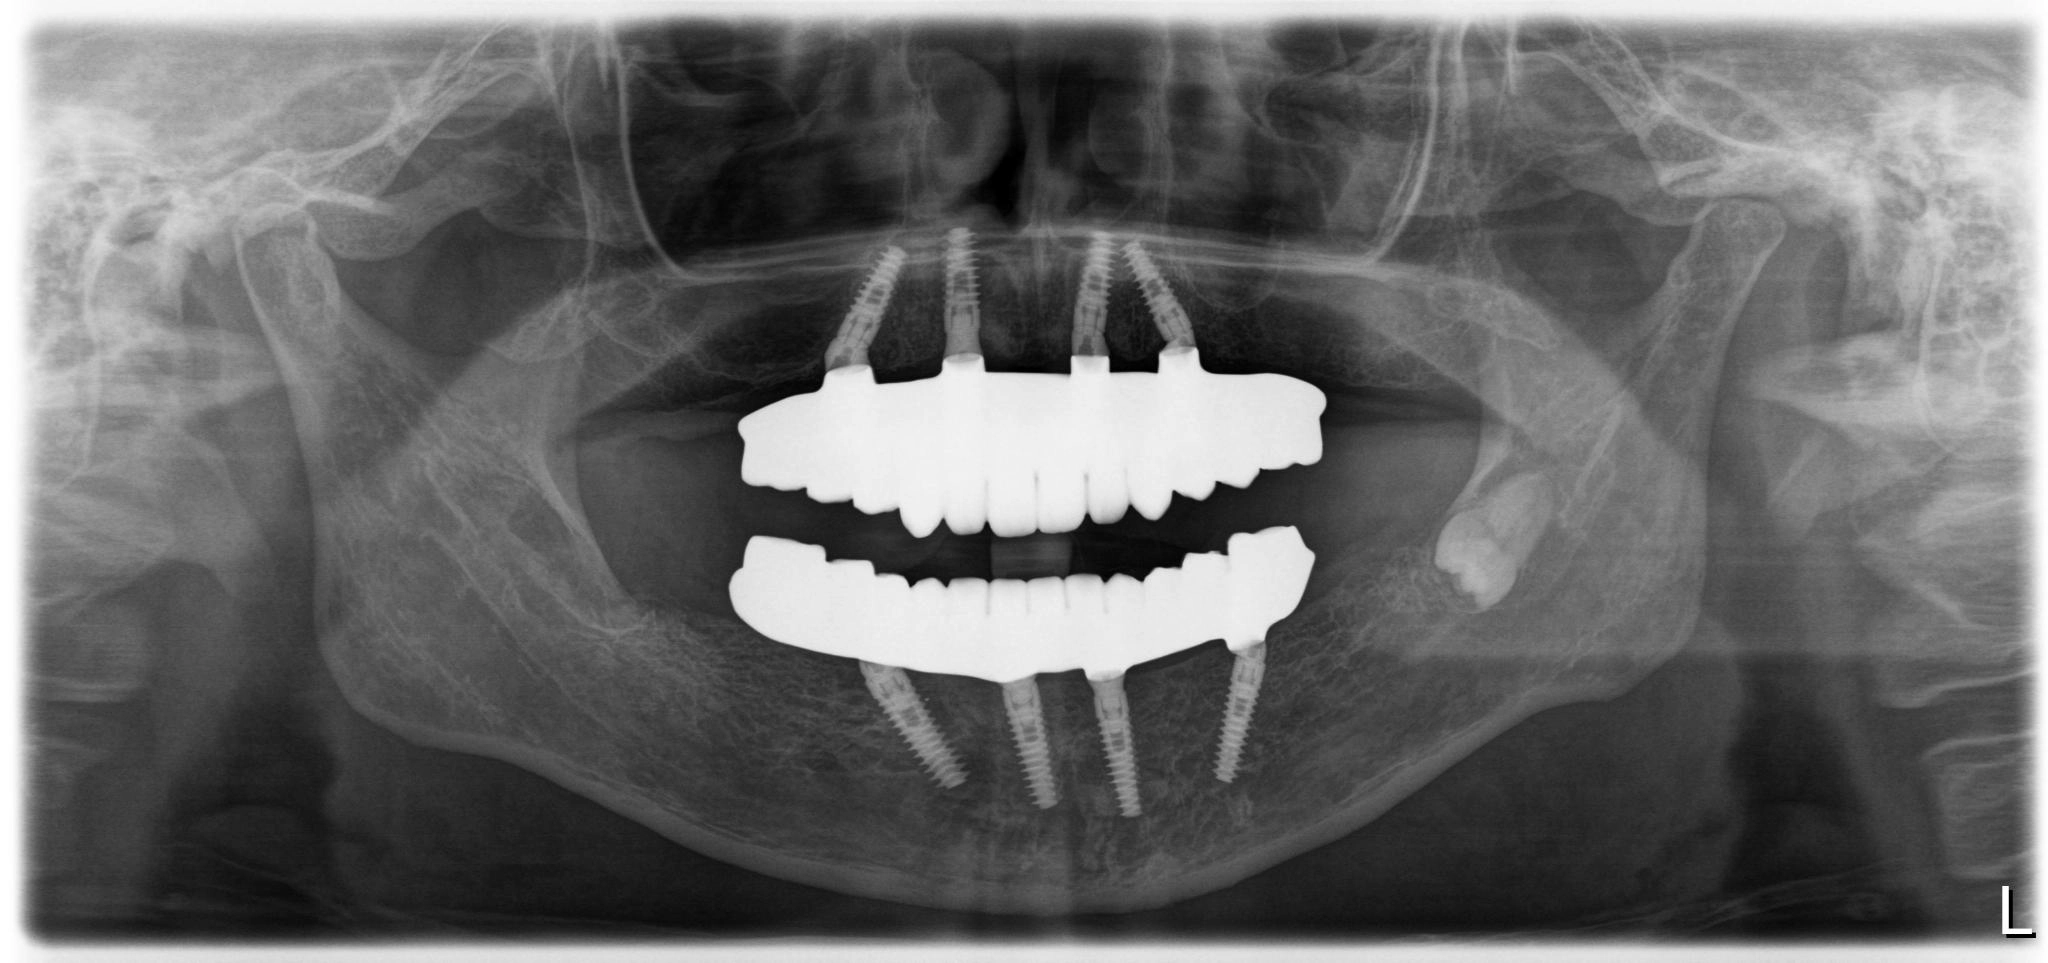

福岡県 46歳(女性)

「根本的な改善をしたい

内容 :上下顎オールオン4ザイゴマ0

費用 :4,822,400円

※モニター価格

期間 :半年

リスク:出血・腫れ・痺れ・痛み

他院で治療を行なっていましたが、根本的な改善には至らないまま不安な状態が続いていました。

カウンセリングで治療の流れや方法について詳しく説明を聞いて手術することを決意しました。

手術前は恐さがあり、緊張していましたが、想像していたような痛みはなく、うたた寝しているような感じでした。気づけば終わっていて、とても満足しています。

元々の自分の歯と比べると仮歯が入った段階でも綺麗になっていて嬉しかったです。この治療法を選んで良かったと思います。